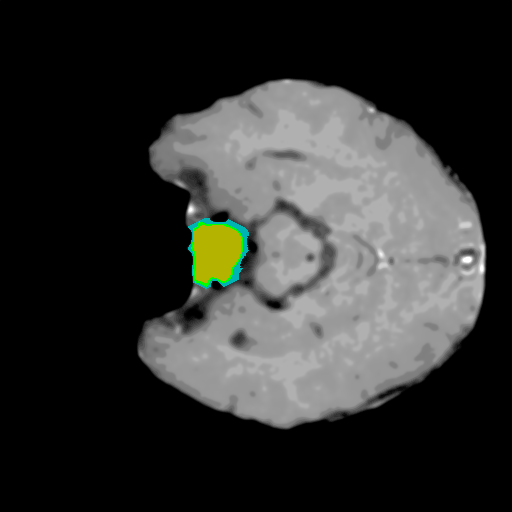

Extensive experiments have been performed in the current setup, and experimental outcomes are reported with the demonstration of numerical and statistical analyses using the proposed QFS-Net, QIS-Net [39], convolutional U-Net [18] and Residual U-Net (URes-Net) architectures [20]. The human expert segmented skull-tripped contrast enhanced DSC brain MR input image slices of size and ROIs are provided in Figure 5 as samples. The demonstration of QFS-Net segmented images followed by the essential post-processed outcome on the slice no. for class level with four distinct activation schemes () are shown in Figure 6. It is evident from the experimental data provided in Table LABEL:tab1 that the proposed QFS-Net performs optimally for the -connected quantum fuzzy pixel information heterogeneity assisted activation () with and gray scale set in comparison with other thresholding schemes and gray scale sets under the four evaluation parameters () [44]. The segmented tumors obtained using the proposed self-supervised procedure under class transition levels with four different thresholding schemes , , and are demonstrated in Figures 7- 8 for the class boundary sets and [39], respectively. The segmented images using the remaining two class boundary sets ( and ) [39] are provided in the supplementary materials section. The segmented ROIs describing the whole tumor region after the masking procedure using QIS-Net, U-Net and URes-Net are also reported in Figure 9.